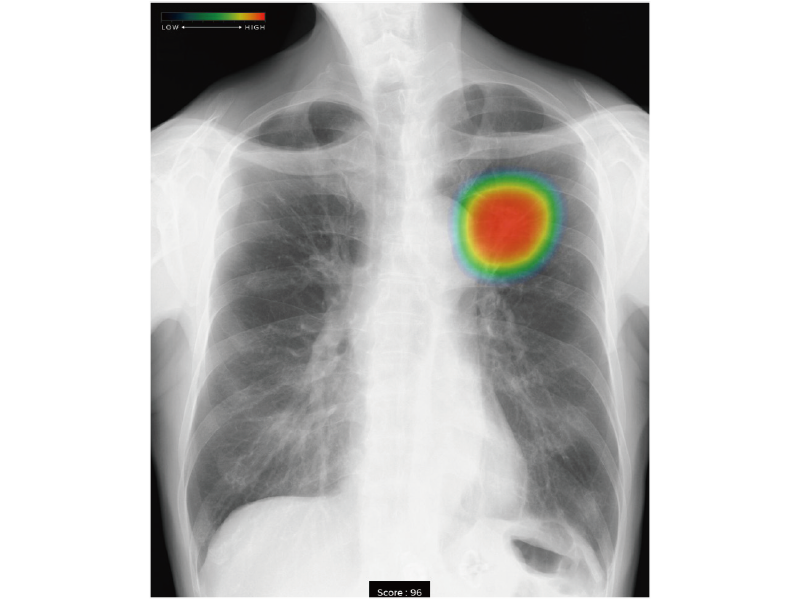

CALNEO Go iQに外部画像処理キットを搭載することで、CALNEO Go iQのコンソール上で胸部X線画像病変検出ソフトウェア「CXR-AID」の解析結果を受信することができます。

- * コンソールでの解析結果の表示は、「CXR-AID」による処理が実施されたことを確認するためのものであり、診断を目的としたものではありません。CXR-AIDの解析結果を利用した読影は画像診断ワークステーションで行う必要があります。

AI技術を活用して開発したソフトウェアです。胸部X線画像を受け取り、解析結果画像を自動的に作成して医師の画像診断を支援します。